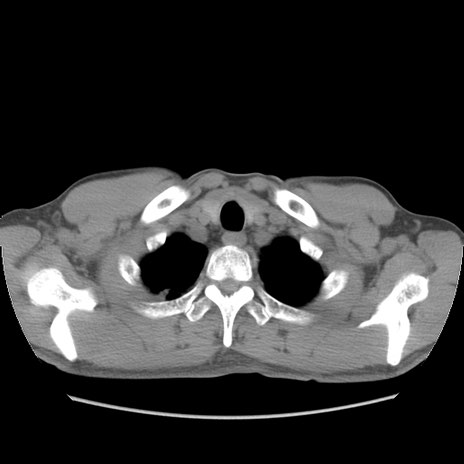

症例56 CT(横断像)

脂肪ウインドウ